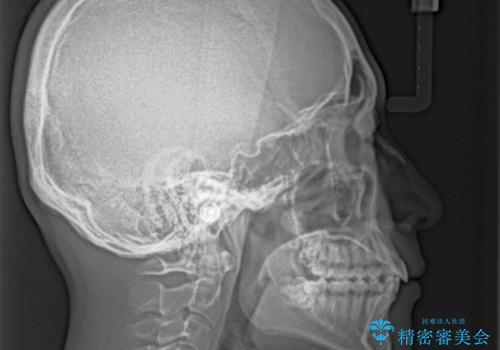

口元はそれほど突出しておらず、患者様自身も気にしていらっしゃいませんでしたが、前歯の捻れやデコボコを解消すると、前方に拡大され、治療後に出っ歯仕上がりとなるリスクがあったため、補助装置により上顎臼歯を後方移動していくこととしました。